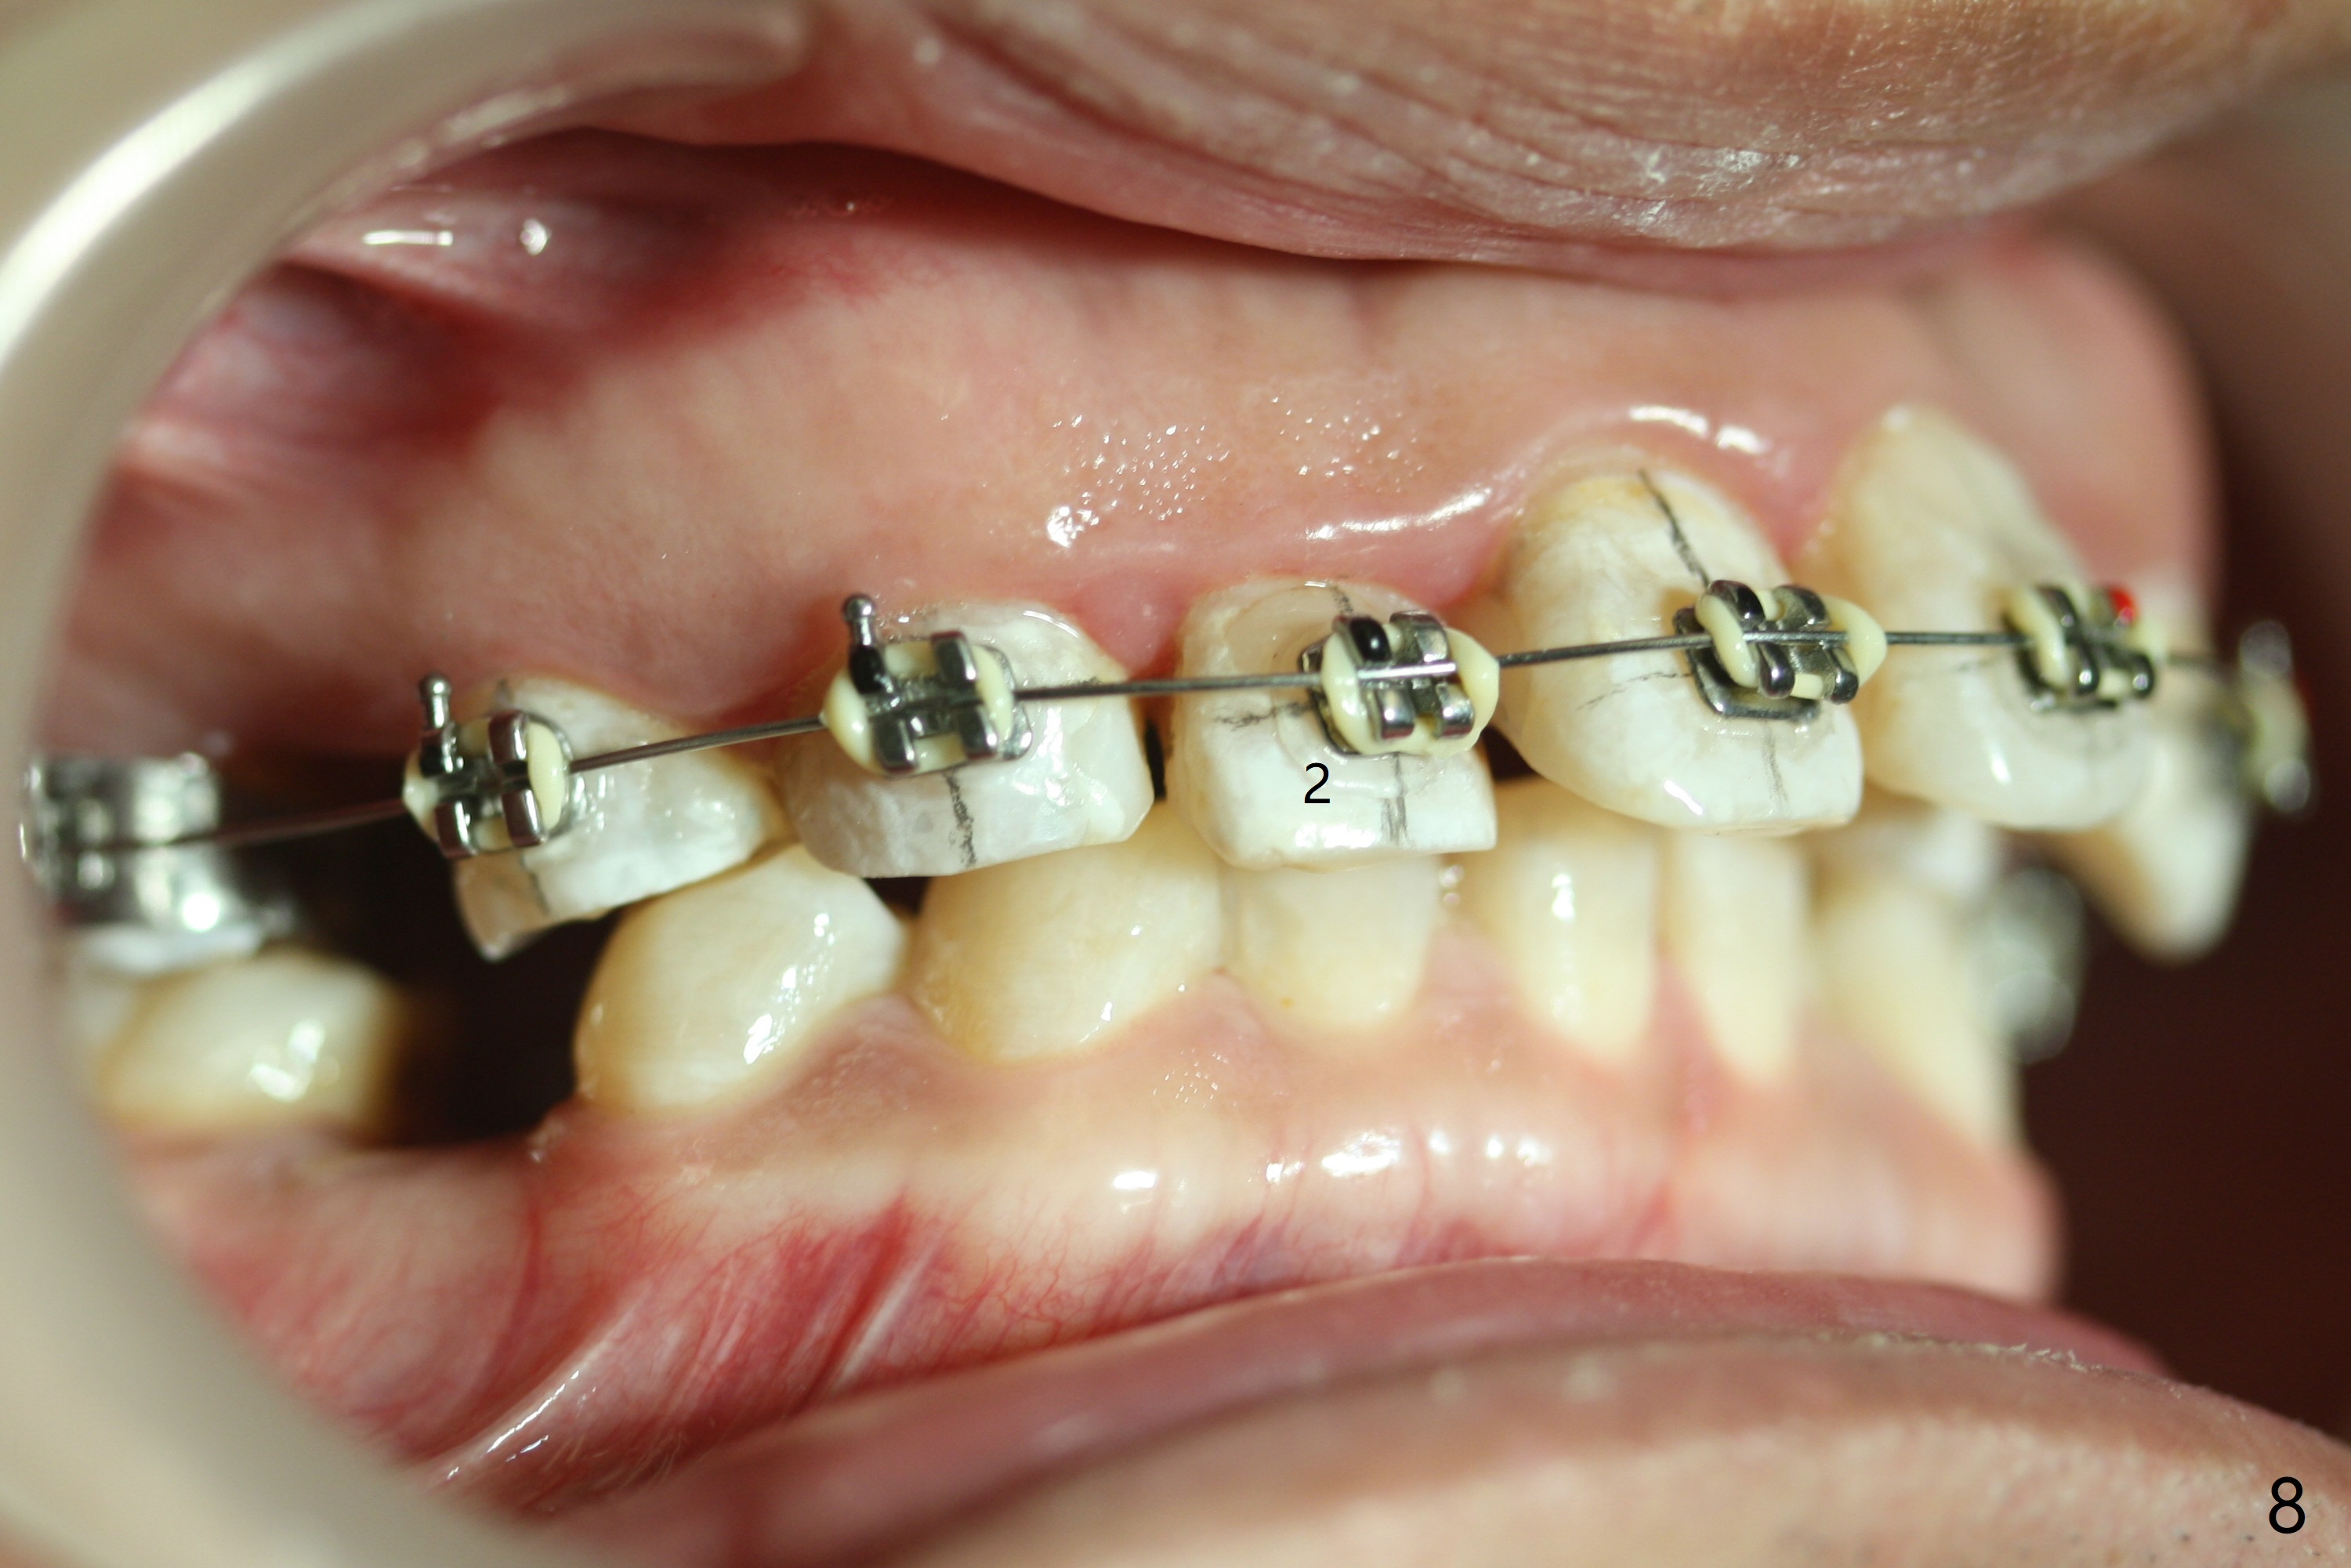

Severe crowding (Fig.1-7) appears to be alleviated especially 2 months after UR5 extraction. Diastemata seem to form mesial and distal to UR2 (Fig.8). Because of severe wear at UR3 (Fig.6), there is no bracket placement differential around it (Fig.8 (14 niti wire)). Lower bands and brackets are placed a week later (Fig.9-11). Because of tight space between LR4 and the opposing tooth (Fig.10), band adhesive is applied to L7 occlusal surface to open the bite (Fig.9). There is an abrupt kink of 12 niti wire between LL4 and 6 (Fig.11). The latter does not improve much in a month; the wires remain the same (Fig.12). For LL2, LR4 has been retracted for ~ 1 month (Fig.13). There is mild tension when 18 ss wire is inserted between LL4 and 6 five point five months post banding (Fig.14). UR4 has been distalized for a month using buccal power chains x3 resulting in rotation; to counter the rotation, a lingual button is placed with power chain x3 lingual and x2 buccal (Fig.15). With space gaining, it is time to finish definitive filling (Fig.16 *). Next visit check midlines, overjet, interdigitation, and molar classification. R4s distalize, but associate with rotation because of power chains buccal and lingual 8 months post banding (Fig.17,18). With the use of the same wires, power chains are applied lingual to continue distalization and rotation correction (Fig.20,21). Lingual buttons are placed at L2s buccalization (Fig.19) and mesialization (Fig.22,23). It appears that space should be created distal to LR3. That is that the lower anterior teeth should be shifted to the right, although it may be not appropriate for the midline.